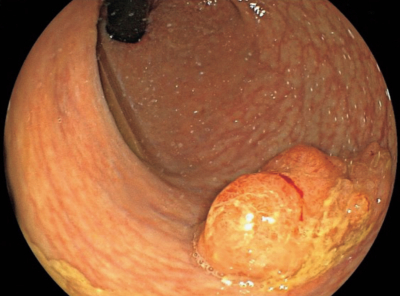

下部消化管内視鏡像を別に示す。

病変が存在する部位はどこか。

a. 直腸

b. 盲腸

c. 上行結腸

d. 横行結腸

e. 下行結腸